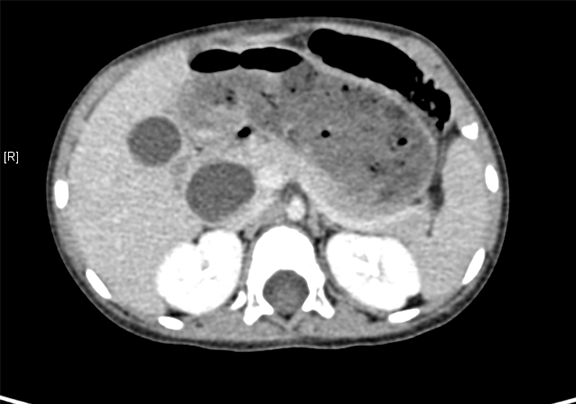

上腹部增强CT:符合先天性胆管扩张(胆总管)。

术前CT检查:

动脉期

静脉期

平衡期